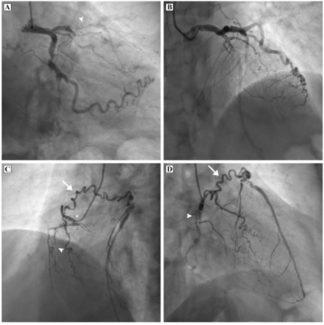

A 63-year-old male patient presented with angina for 6 months with recent aggravation of symptoms. Physical examination was unremarkable. The electrocardiogram was within normal limits, cardiac troponin levels were not elevated, and left...